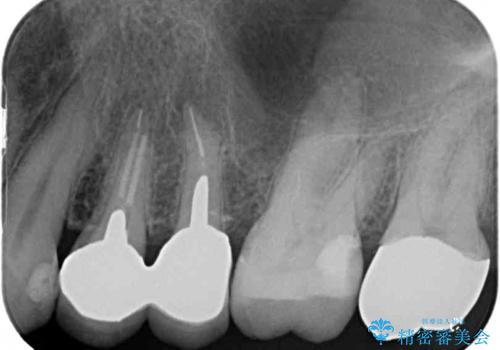

- 歯肉が退縮したためにクラウンの縁や歯根が見えてしまっていることを気にして来院された患者様です。

また、歯肉が黒く変色していることも気になるとのことでした。

仮歯に変える際に歯肉の一部を切除し、金属片による変色を除去した後、オールセラミッククラウンにて補綴することとしました。

メタルタトゥー(金属イオンの溶出による歯肉の変色)は、歯に装着された金属から金属イオンが溶け出したり、金属を除去するときの切削片が歯肉に入り込んでしまったりして引き起こされます。